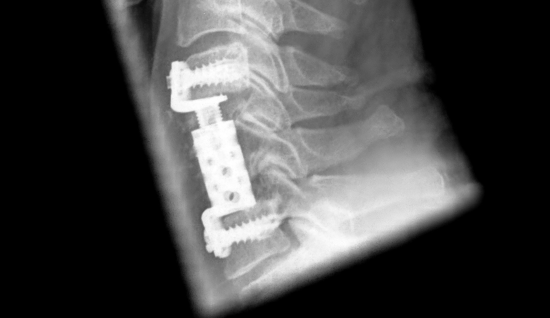

Corpectomy C5 and C6 and vertebral body replacement for stenosis and myelopathy

Corpectomy C5 + 6, decompression and vertebral body replacement. Good assessibility of the spinal canal and spinal cord despite titanium implant.

The MRI demonstrated high-grade degenerative spinal canal stenosis of C4-7 with compression of the already somewhat atrophic spinal cord as well as intramedullary spinal accentuation in T2 weighting as signs of myelopathy. The CT demonstrated extensive stenosis of the cervical spine due to dorsal osteophytes at the level of C4/5, C5/6 and C6/7 and ligamentous narrowing. In view of the myelopathy seen clinically and on imaging, an indication was made for a more extensive decompression of the cervical spinal canal. This should be achieved from the anterior direction via a corpectomy of C5 and C6 and vertebral body replacement implant with expandable screws.